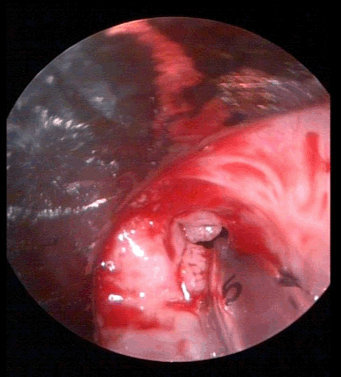

A preterm male infant was delivered by lower uterine cesarean section, with a history of polyhydramnios in the mother. The newborn infant developed repeated episodes of vomiting with regurgitation of feeds since birth. A diagnosis of congenital pyloric atresia was made for which he underwent gastroduodenostomy (Figure 1) on the fifth day of life. He also developed bullous lesions over the trunk and extremities, with new lesions developing with trivial trauma (Figure 2) (Figure 3). At six months of age, the child developed poor stream of urine with discharge of whitish flecks with fever. Urine culture was positive for Pseudomonas aeruginosa, sensitive to gentamicin. Ultrasound showed hydronephrotic changes in both kidneys with dilatation of bilateral ureters. He was diagnosed to have posterior urethral valve (Figure 4) for which vesicostomy (Figure 5) had to be done after attempts of cystoscopy guided valve fulguration were deemed ineffective in a setting of recurrent urinary tract infection and hydronephrosis. The child presented with respiratory distress and hoarseness at four and a half years of age. Thereafter, direct laryngoscopy was done which revealed multiple masses occupying bilateral false cords, left aryepiglottic fold and anterior commissure (Figure 6). The masses were firm, fleshy, pedunculated and did not bleed on touch. Biopsy was taken and surgical excision of the masses was done. The histopathology examination revealed squamous papilloma (Figure 7). The child again presented with acute severe respiratory distress with cyanosis two months following discharge, for which emergency tracheostomy had to be done. Attempts of weaning were tried but the child was unable to tolerate it. At present, the child is 9.5-year-old, tracheostomized, school-going with age-appropriate neurodevelopment. His 6.5-year-old sister underwent gastroduodenostomy for congenital pyloric atresia on 21st day of life and vesicostomy for posterior urethral valve at two years of age. She was also diagnosed with junctional epidermolysis bullosa at four years of age. The mother of the patient also suffered from polyhydramnios during the birth of her second child. There is a history of sibling death within first week of life in his father’s generation following a blistering disorder.

Figure 6: Fleshy masses in bilateral false cords, left aryepiglottic fold and anterior commissure.